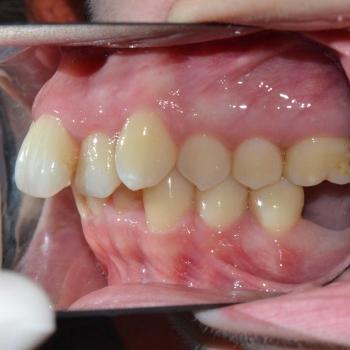

Tünde a felső fogív torlódása, illetve az alsó metszőfogak között található rések miatt keresett fel. Az első találkozásunk alkalmával azonban fény derült a középvonalak eltolódására, enyhe mélyharapásra, a felső metszőfogak túlzott elülső pozíciójára, illetve a régóta hiányzó alsó 6-os fog helyének beszűkülésére is, így a kezelési terv ezen problémák megoldására is kitért.

Tünde végül úgy döntött, hogy nem csak az esztétikai, de a funkciós problémák is szeretné megoldani, melyhez hagyományos fém fogszabályozót választott. A fogszabályozáshoz különböző kiegészítőket is igénybe vettünk úgy, mint harapásemelő, különböző intermaxillaris gumihúzások, illetve egy speciális szájpadi mini-implantátum a hozzá kapcsolódó transpalatinalis ívvel (hibrid transpalatinal ív), ami minimalizálta a hátsó fogak mozgását, miközben a felső metszőfogak hátrafele mozogtak.

A kezelés végére minden problémát sikerült megoldanunk, a középvonalak korrekcióját leszámítva. Ennek ellenére, mivel a felső középvonal az arc tengelyében helyezkedik el, az esztétikai eredmény nem csorbult és a funkciót sem befolyásolta. A jobb alsó 6-os fog implantációs pótlása a fogszabályozás befejeztével kezdődött meg.